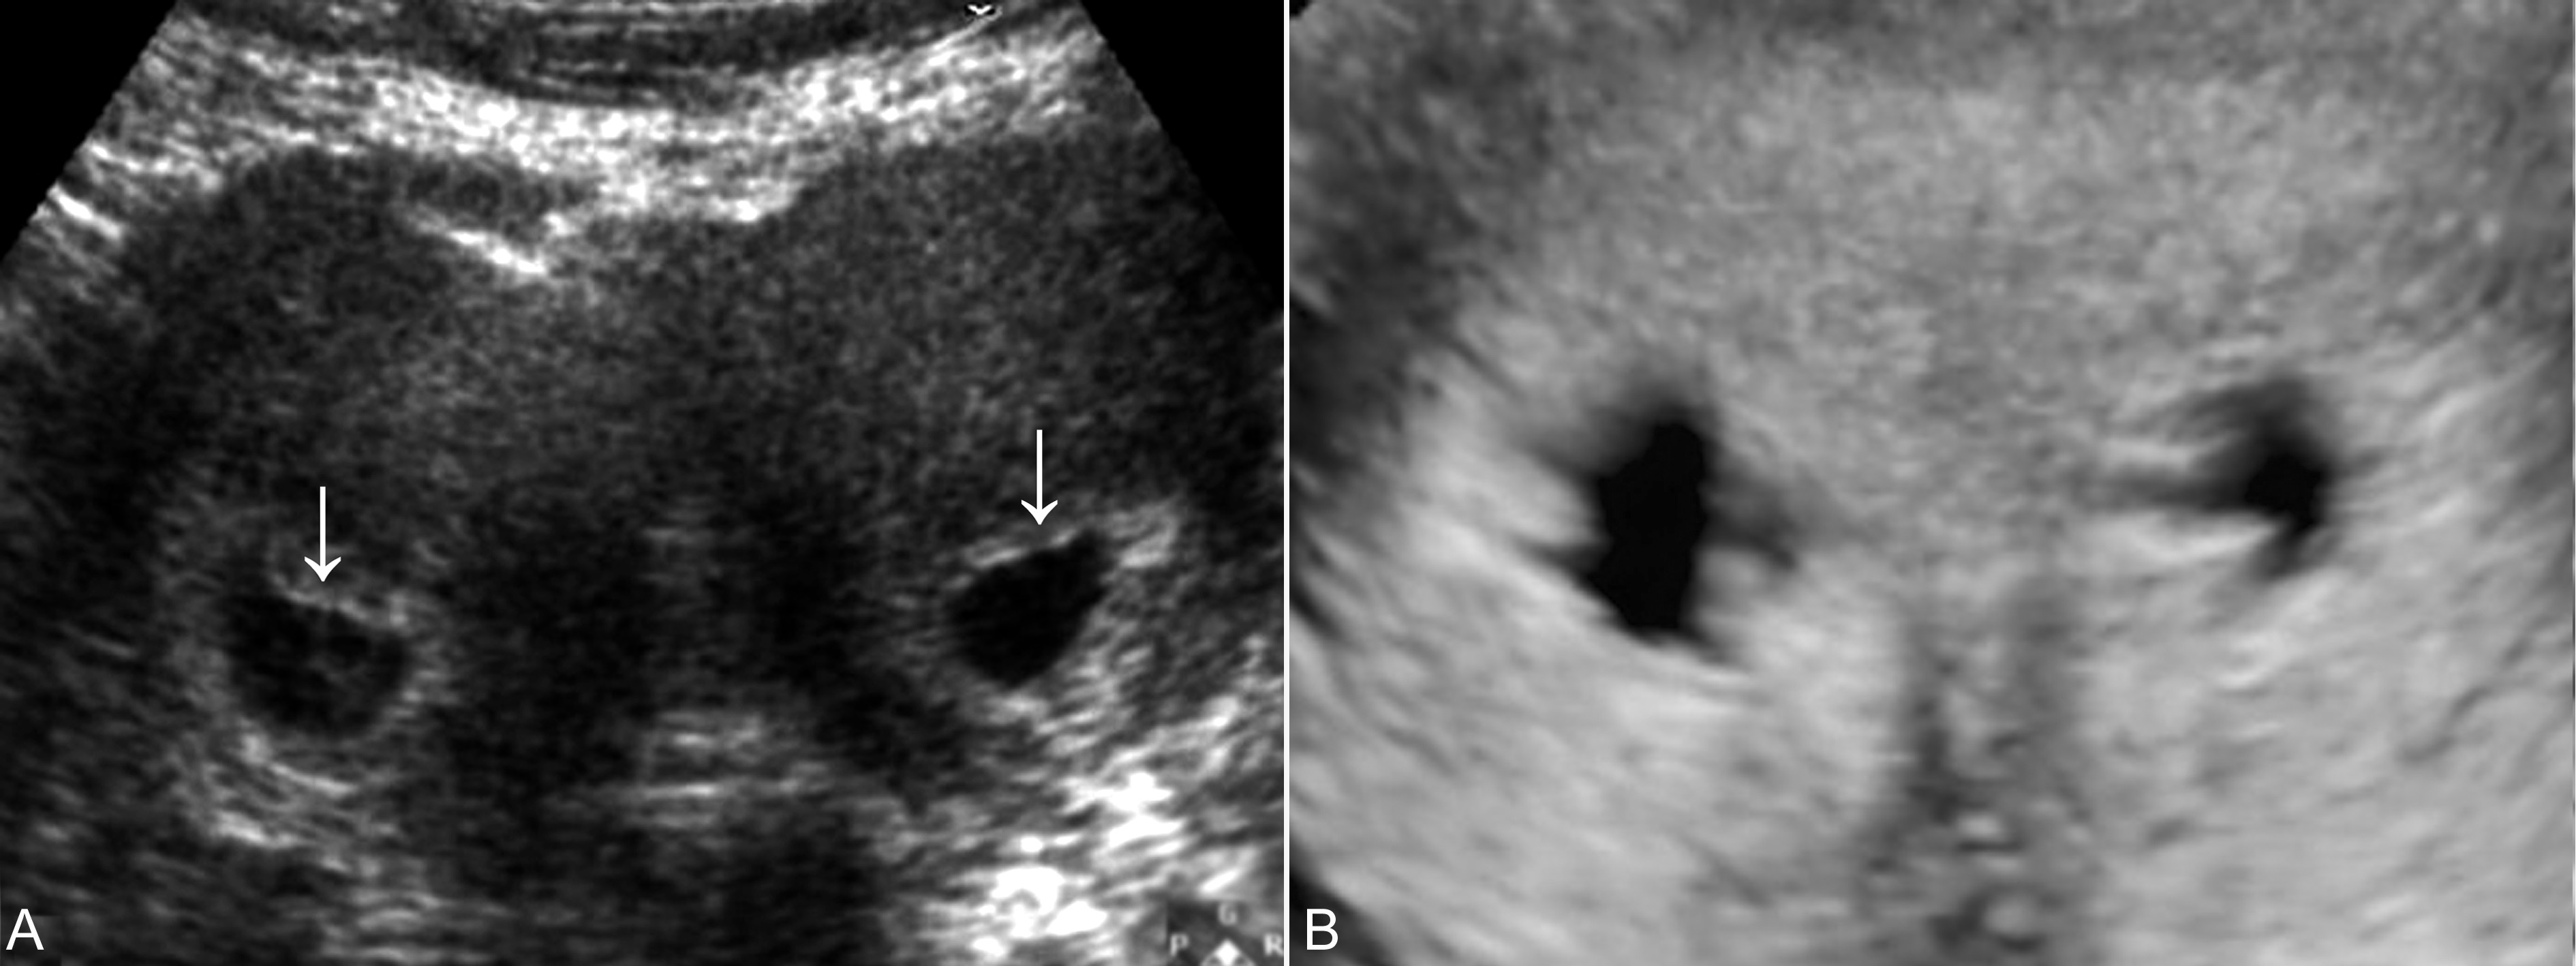

早期妊娠超声显象检查可以显示双侧的子宫体,其中之一内可见孕囊及胚胎回声,另一侧子宫明显增大(图2),内膜回声增强、增厚,有时可在未妊娠的一侧子宫腔内显示细长的无回声区或由增厚的蜕膜形成的强回声。在做出双子宫、一侧子宫妊娠的诊断时应当注意与妊娠合并子宫肌瘤、残角子宫等进行鉴别。一般情况下,子宫肌瘤与子宫肌壁回声有一定的差异,或回声增强,或回声降低,内部很少可以显示规则的囊状无回声区。如果在双侧子宫内均显示孕囊回声,则为双子宫、双侧妊娠(图3)。

图3双子宫双侧妊娠(箭头)声像图(A)及三维显示(B)